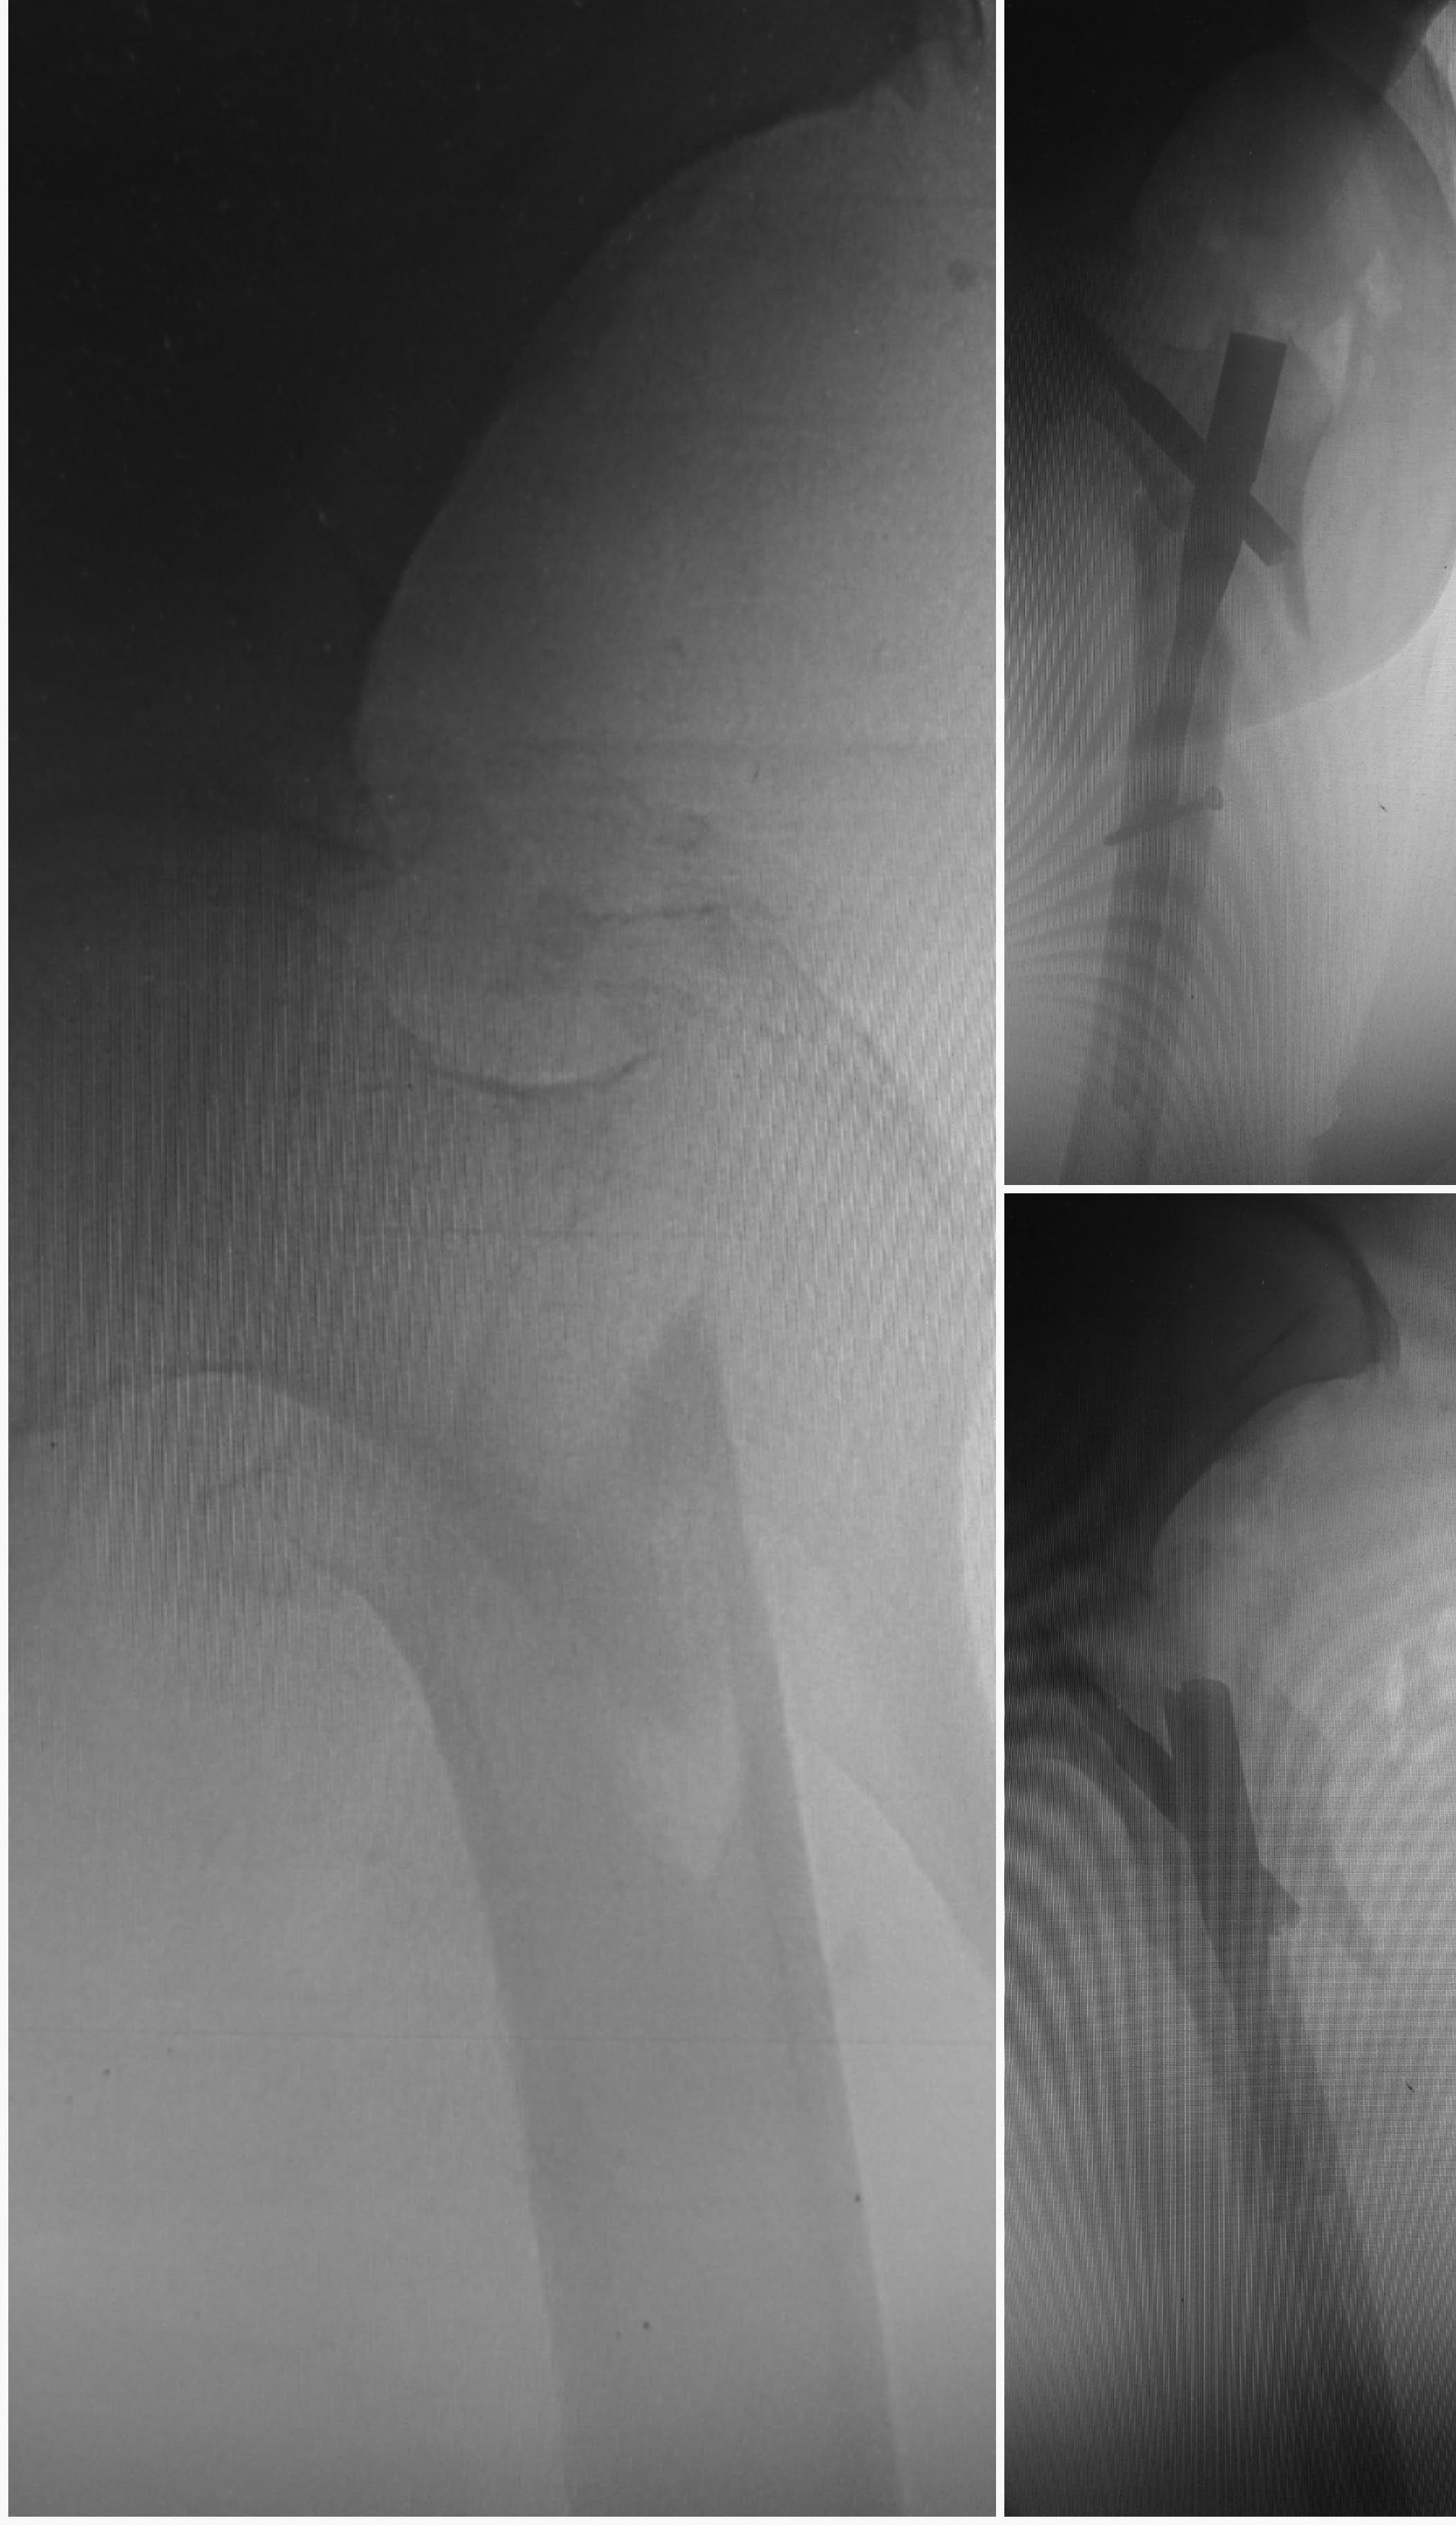

Больная, 90 лет. Остеосинтез Y-PFN. Переделывать не планируется. Репозиция до введения гвоздя не быда достигнута. На будущее, что нужно при таком переломе делать, чтобы достичь репозиции. Спасибо.